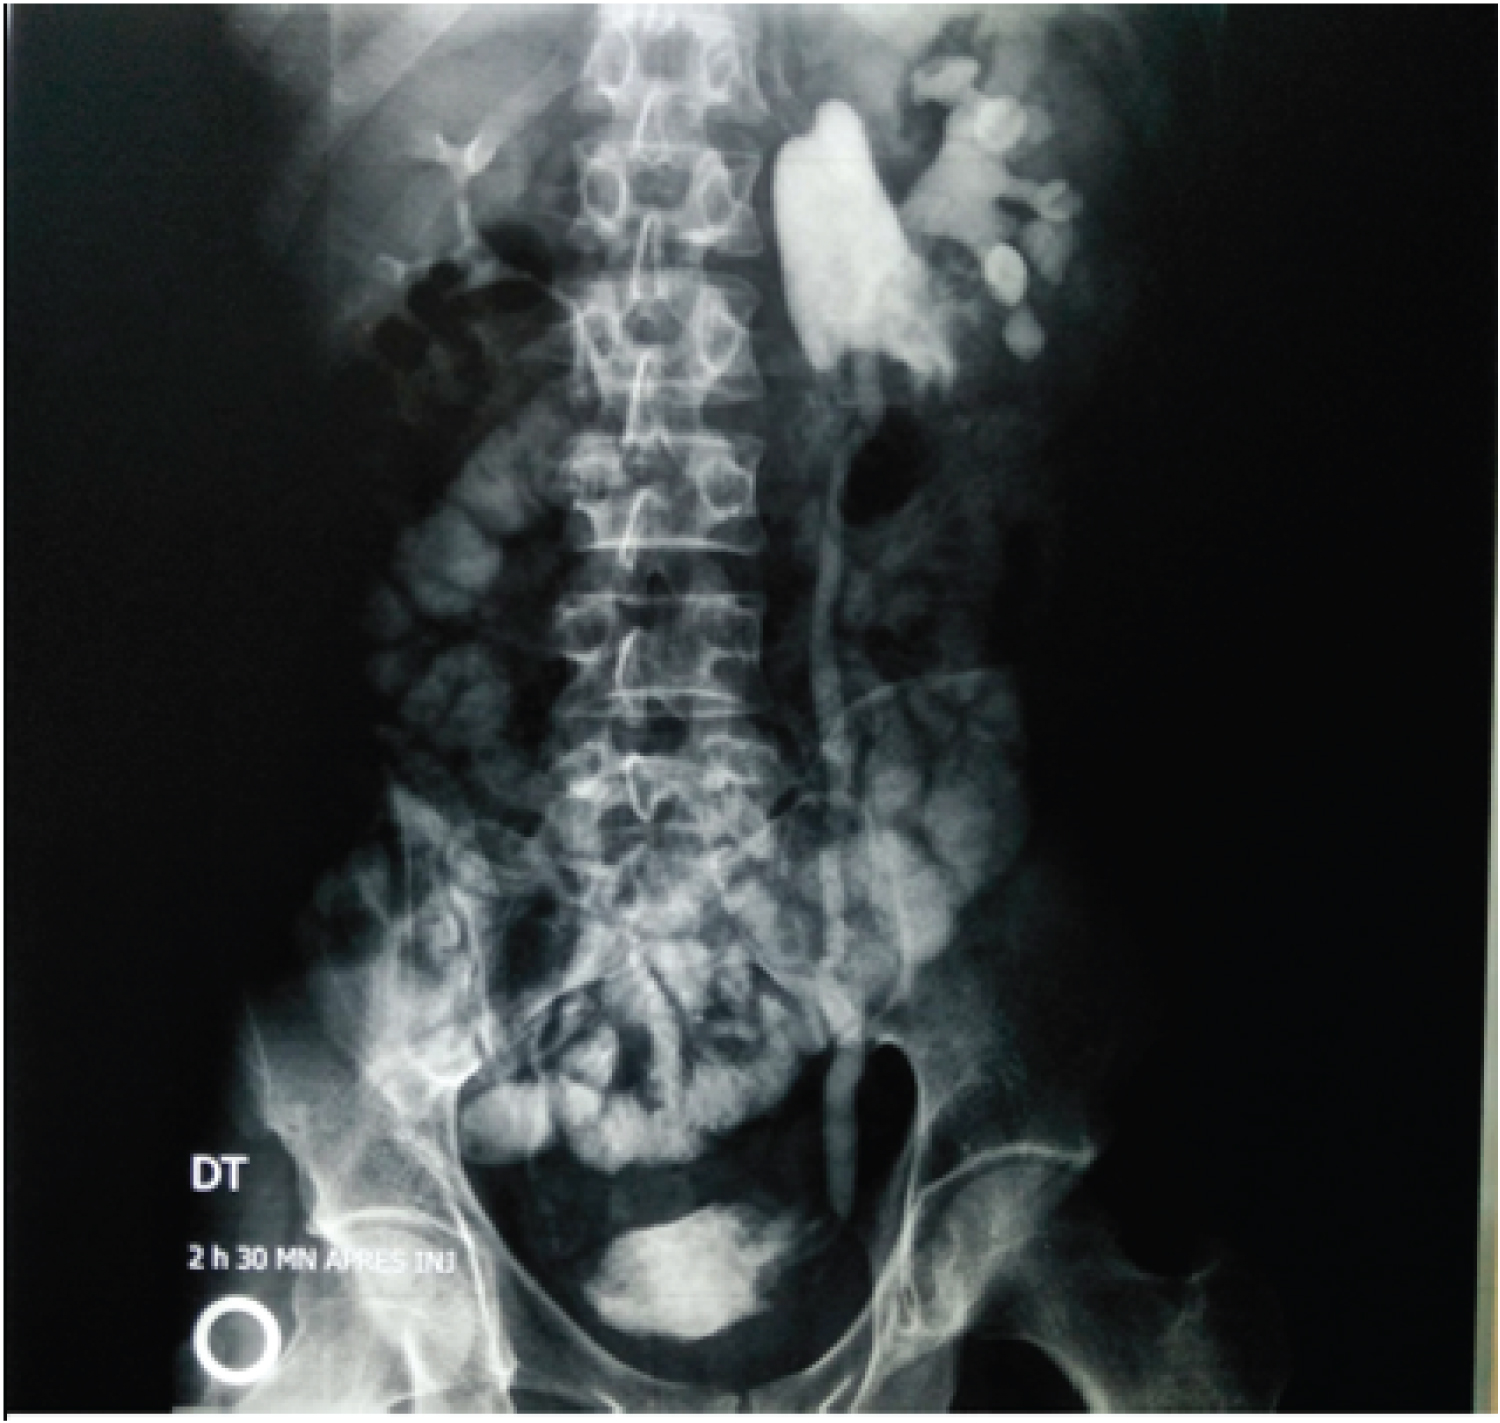

A 40-year-old man with left lumbar penetrating trauma 30 days ago.

On the day of trauma, the urgency surgeon repaired multiple ileal injuries, and the patient returned home (Figure 1).

We readmitted the patient because of left lumbar pain and sped up transit.

Ultrasonography showed a retroperitoneal collection.

Urography showed ureteral enteric communication.

Figure 1: Post trauma fistulae.